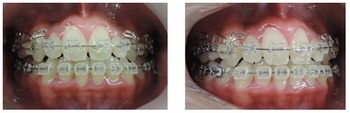

大人の矯正治療は出来るだけ見えにくい小さな矯正装置を利用して上の歯並びから歯ならび治していきます。埋伏している犬歯も萌出させていきます。

上顎の歯列がある程度改善してから下顎の歯列を見えにくいブラケットという矯正装置で整えていきます。埋伏している犬歯も萌出させていきます。

MEAW(マルチループ)により咬合高径(咬み合わせの高さ)を改善して美しい咬み合わせに治療していきます。(矯正開始から3カ月後)

終了時2か月前(1年3ヶ月後)

終了時(開始から1年8カ月後)

こどもの時から歯並びだけではなく上下顎骨に歪みがある症例です。

早期治療で上下顎骨や咬み合わせの高さを改善していたので素晴らしい歯並びになりました。

もしも早期治療をしないで大人になってから治療を開始したとすれば非抜歯での治療が困難となってしまう事もあるので早期治療をお勧めします。